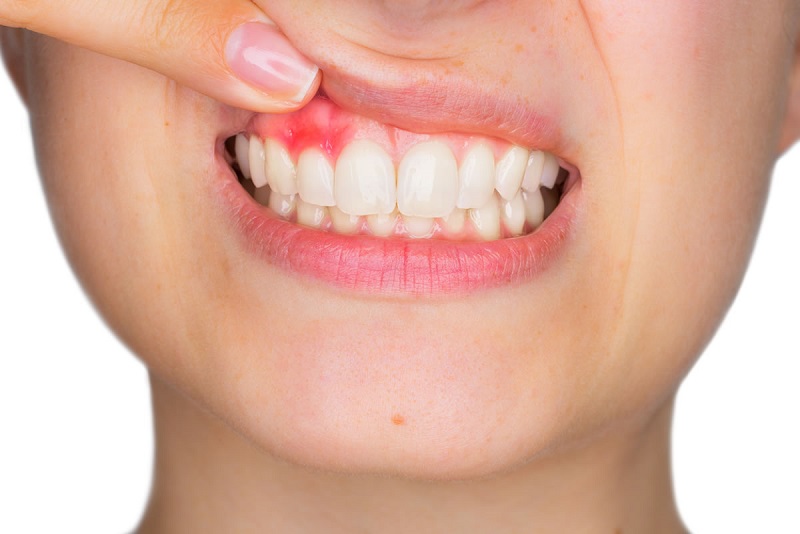

Ngoài ra, tình trạng viêm lợi cũng cần được xem xét. Nếu khu vực quanh vùng mất răng có dấu hiệu viêm nhiễm, việc thực hiện cầu răng sứ có thể gây ra các biến chứng nghiêm trọng và không đạt được hiệu quả như mong muốn.

Nếu các răng trụ không đủ khỏe mạnh, có dấu hiệu viêm tủy, hoặc là viêm lợi nặng, việc thực hiện cầu răng sứ có thể gây ra nhiều biến chứng. Những tình trạng này có thể làm ảnh hưởng đến sự chắc chắn và ổn định của cầu răng trong miệng.